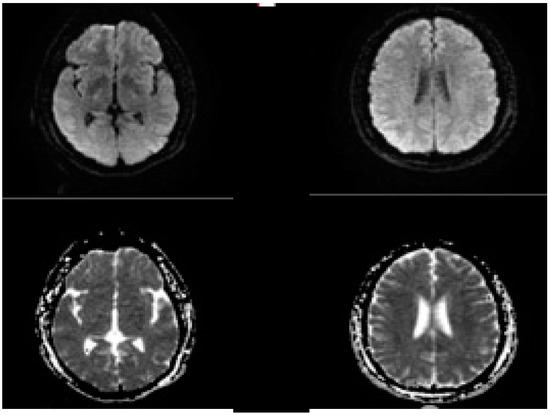

2.5. Evolution of the Concept of the Tissue Window and Late Window Trials